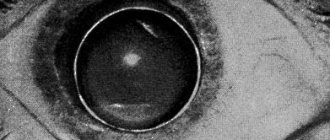

General description Lens luxation is a complete or partial (luxation or subluxation) dislocation of the lens